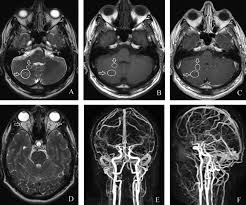

Beyin manyetik rezonans görüntüleme (MRI) ve tekrarlayan stimülasyon içeren elektrofizyolojik çalışmalar normaldi. Sifiliz kan ve beyin omurilik sıvısı (BOS) örneği ile teşhis edildi. Uzun süre, yüksek doz intravenöz penisilin ile tedavi edildi. Oküler bulgular merkezi sinir sistemi tutulumunda nörosifilizin önemli bir göstergesidir. Hastalığın birincil etkisine bağlı oküler tutulum nadirdir. Menenjit ile ilişkili beyin omurilik sıvısı emilim bozukluğu gelişirse, göz hareket bozukluğu ve gözbebeği anormallikleri ortaya çıkabilir. Nörosifiliz tanısı, farklı klinik belirtiler nedeniyle gecikebilir. Nörosifiliz de oküler bulgularda dikkate alınmalıdır.